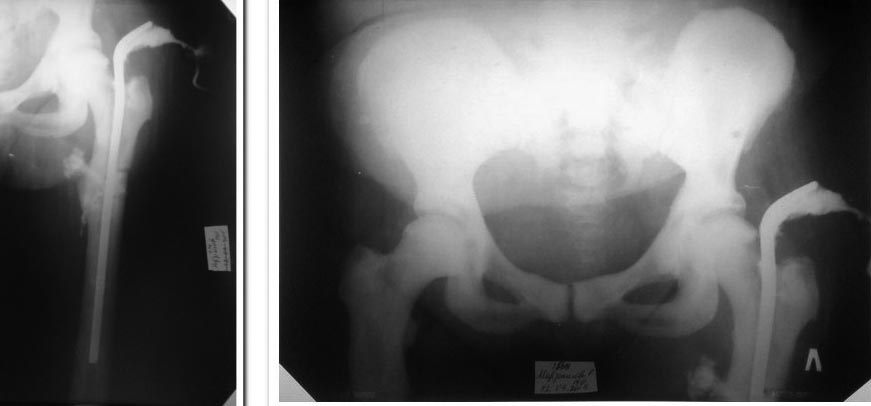

Прошу помощи с тактикой лечения больной А., 54 лет. Госпитализирована

с диагнозом:«сросшийся синтезированный перелом верхней трети левого

бедра. Осл: металогранулёма. Соп: сахарный диабет 2 типа»  Из анамнеза

оперирована в октябре 2013г. в ЦРБ по месту жительства по поводу

перелома в/з лев. бедра. Травма бытовая. Со слов леч. врача и пациентки

планировали БИОС, но из-за технических трудностей обошлись штифтом ЦИТО.

П/о период без осложнений, по заживлению наложена кокситная гипсовая

повязка сроком на 2 мес. По снятию г/повязки на 3 мес. после операции в

области верхушки вертела образовалась флегмона, которая вскрыта.

Сформировался свищ, который до сих пор функционирует. В августе 2014г. в

отделении по месту жительства (где был произведён остеосинтез) и

повторно в январе 2015г. в другом мед. учреждении была произведена

операция ревизия свища, попытка удаления штифта, которая не увенчалась

успехом.

На наш взгляд у больной имеет место заболевание«мраморная болезнь. На

снимках с фистулографией  видны характерные изменения остеопетроза

костей. Посовещавшись с коллегами мы пришли к мнению, что штифт удалить

надо, а для этого придётся продольно распилить диафиз бедра циркулярной

пилой ниже области перелома. Какие будут мнения на этот счёт? Не

произойдёт ли повторный перелом?